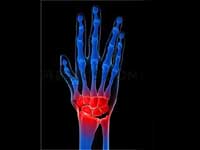

Vitamin-D Deficiency Leads To Rheumatoid Arthritis

Females living in the north eastern United States are more likely to develop rheumatoid arthritis, suggesting a link between the auto immune disease and vitamin D deficiency.

RA is a chronic inflammatory disease that affects the lining of the joints, mostly in the hands and knees. This chronic arthritis is characterized by swelling and redness and can wear down the cartilage between bones. RA is more common in women than in men.